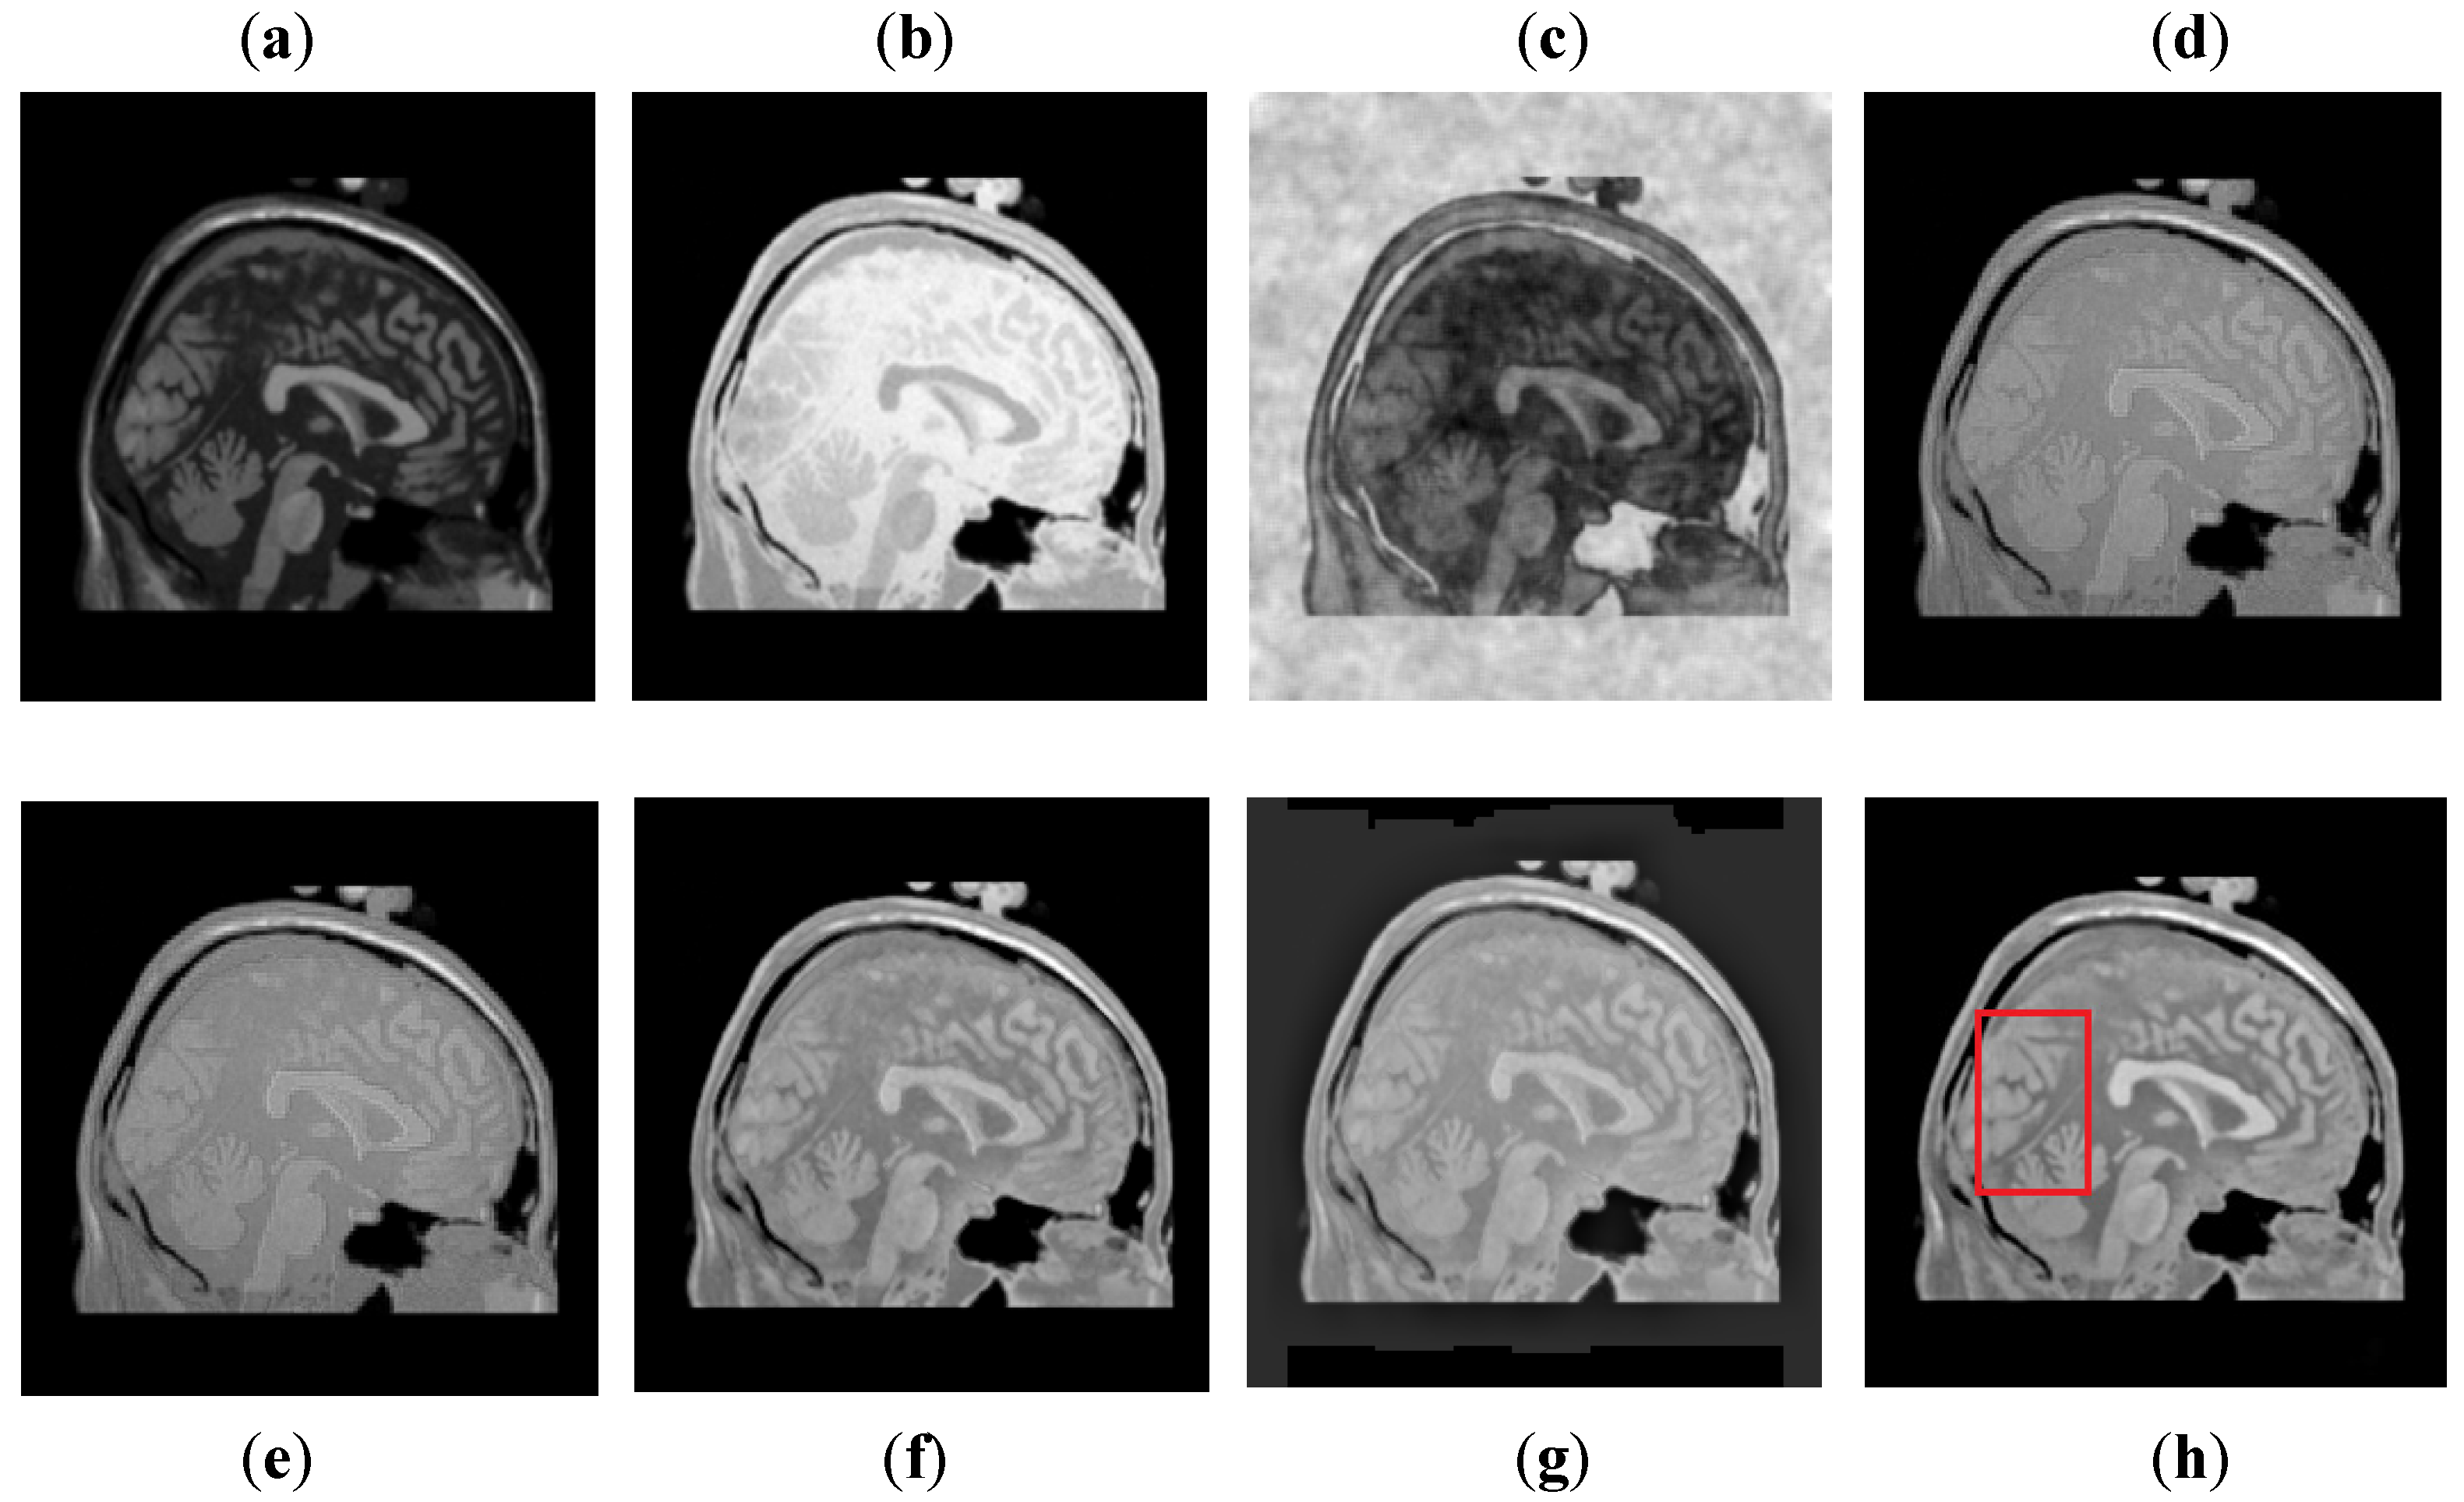

It can be visually observed in Figure 9 that the DCT method has more artifacts that distort the overall quality of a fused image. The DWT and NSST-SF-PCNN produce almost similar results, but DWT has more contrast and less noise than NSST-SF-PCNN. However, both methods have poor detailed and structured information that significantly loses valuable information about soft tissues. The CSR method effectively captures more information from the CT image, but due to non-uniform illumination, it drastically fails to restore more information about soft tissues from MRI image. On the other hand, the CNN method retains most of the information about soft tissues from an MRI image with good contrast, but it cannot completely capture edges and boundaries from a CT image that affect the image quality. The proposed method shows its superiority over other methods by producing a fused image that contains information from both source images. It has better contrast with very negligible artifacts. Additionally, it can be further explored from red boxes that the proposed method can effectively retain the soft tissues from MRI image and preserve bright and sharp detail about bones from a CT image.

Figure 9. Data-3: (a) CT image, (b) MRI image, (c) DCT, (d) DWT, (e) NSST-SFT-PCNN, (f) CSR, (g) CNN, and (h) Proposed.